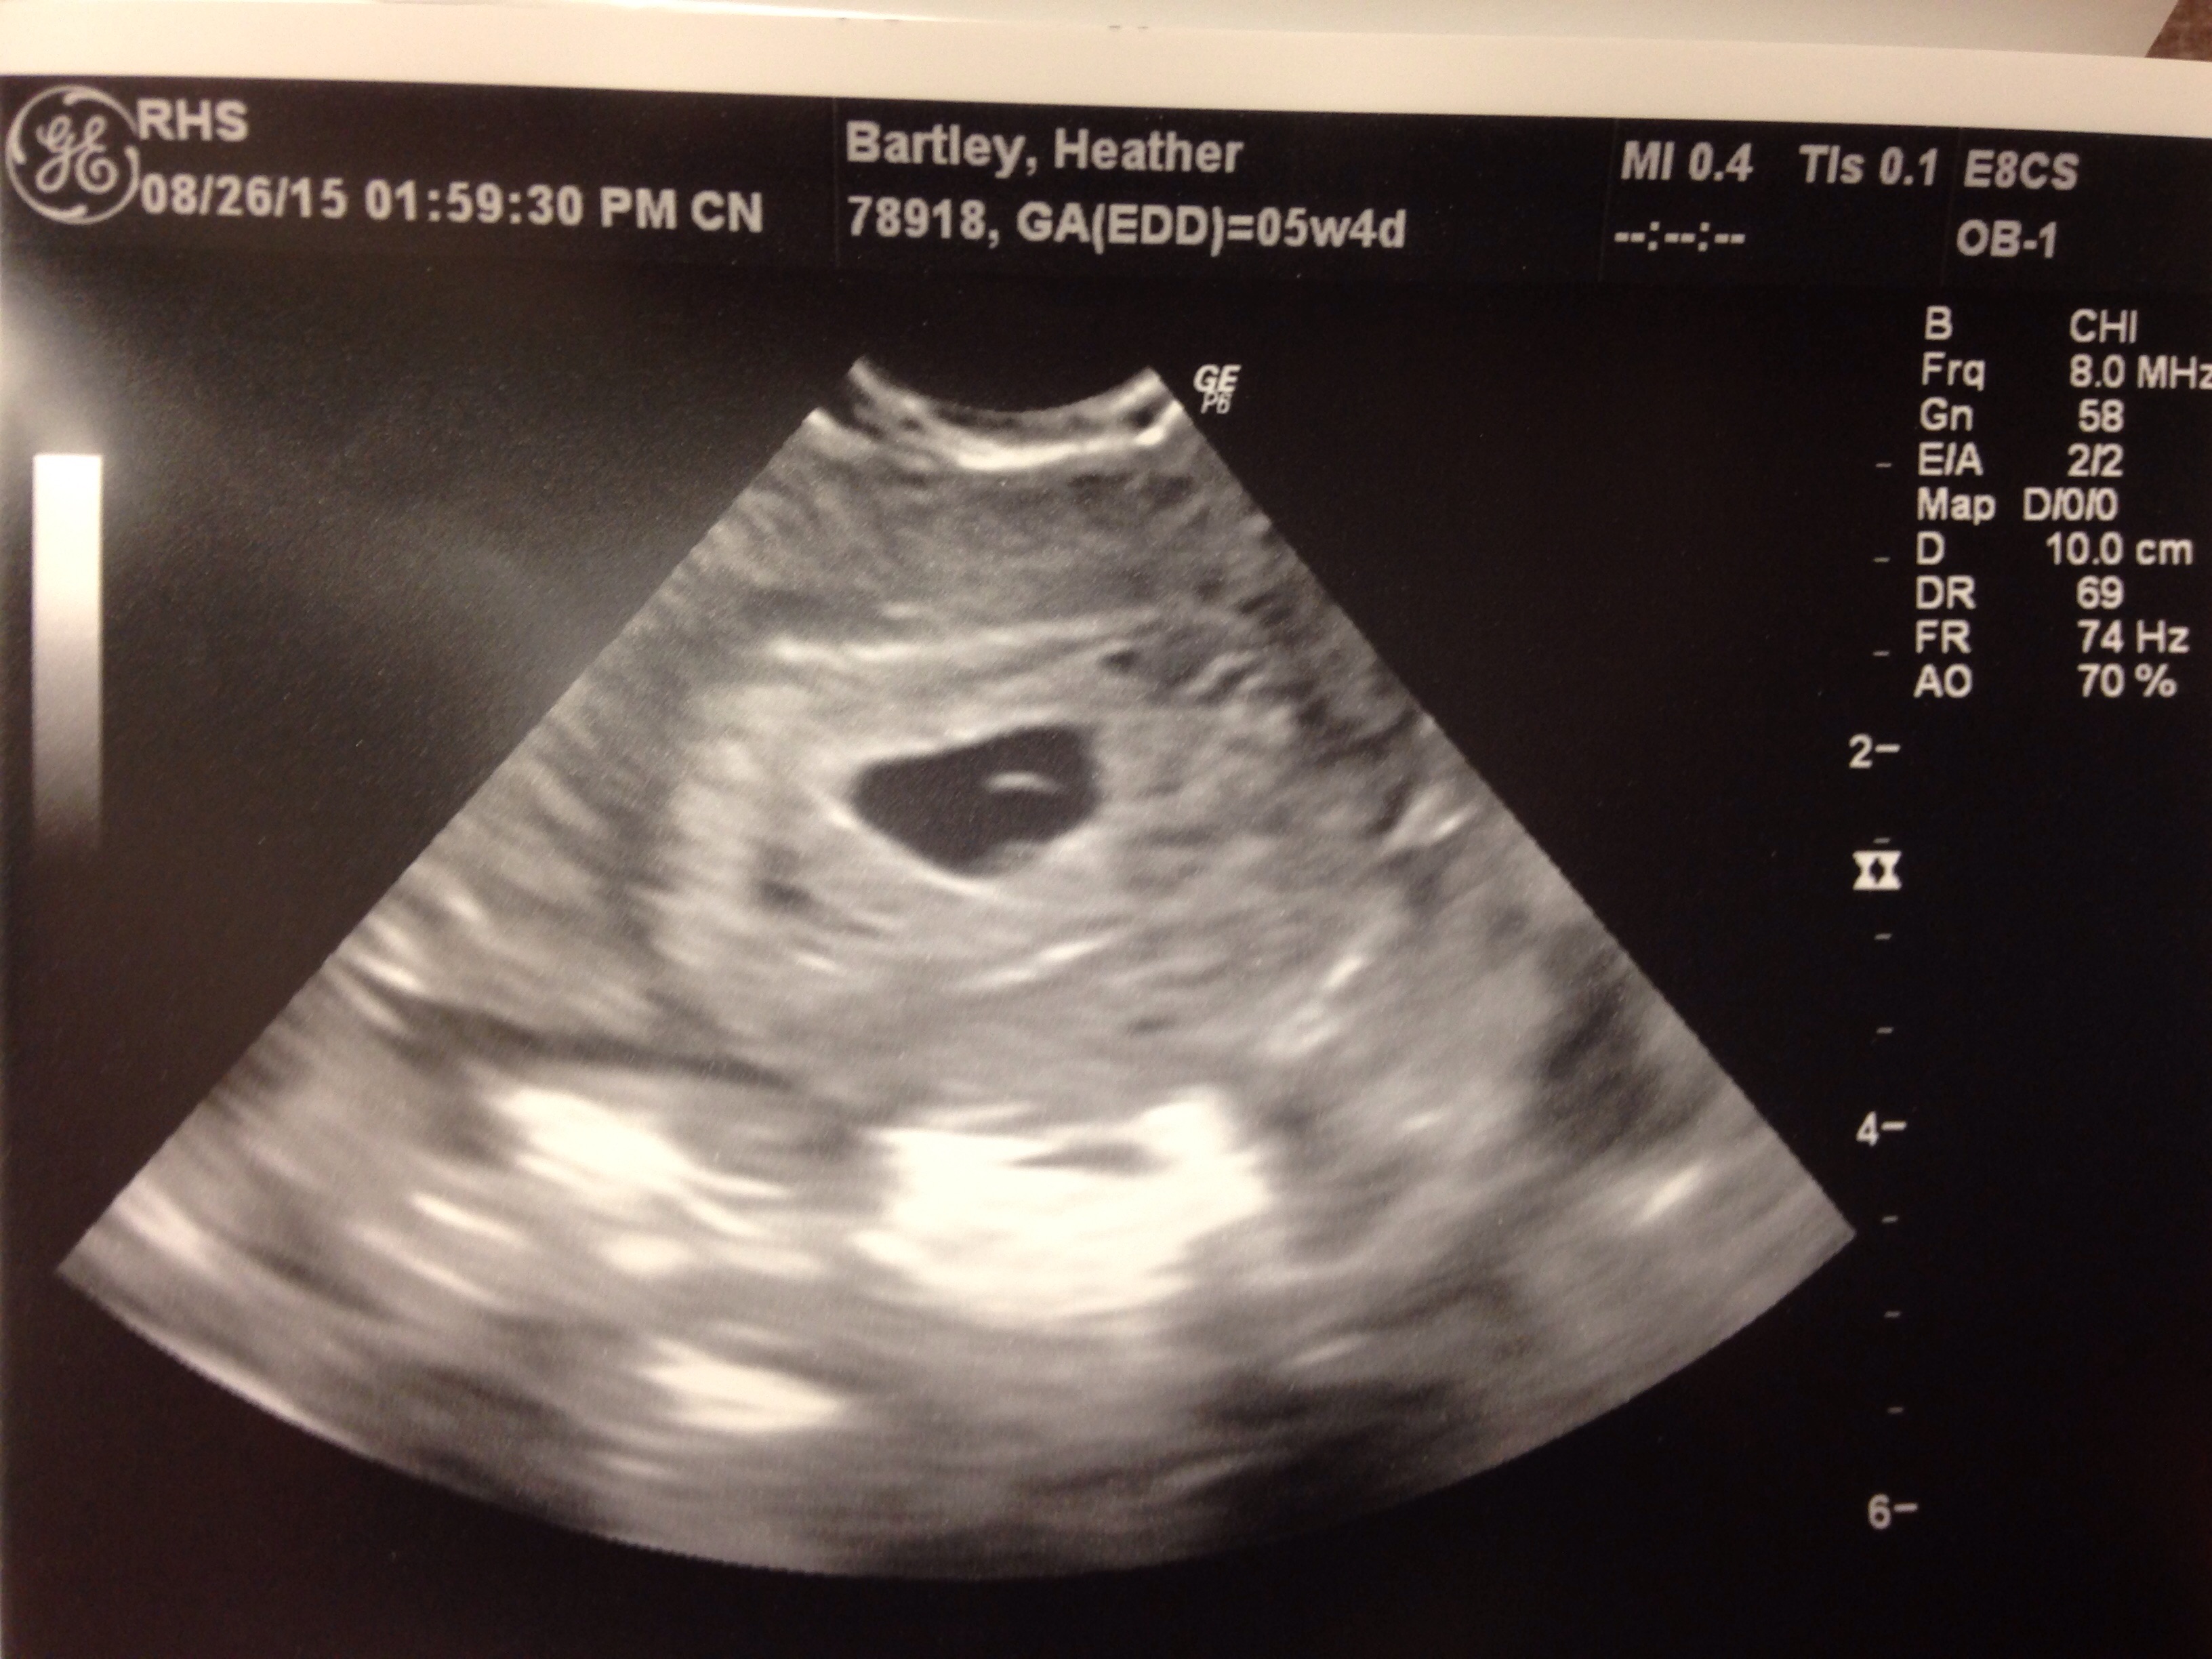

Just got this yesterday our first ultrasound of our babe! The little black dot in the white space on the left. I was on 5w3d. I go back next Tuesday so I'll be 6w4d and hopefully we'll get to see/hear the heartbeat then!